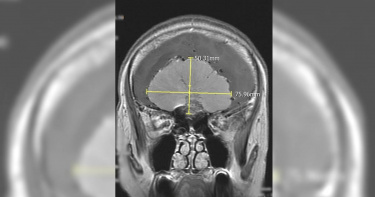

65歲吳小姐最近幾年來,時常感覺頭痛、頭暈與視力模糊,到眼科診所檢查結果為眼壓過高,再接受眼科診所建議去大型醫院檢查後,才偶然發現右側前額葉有一顆直徑9公分的巨大腦膜瘤,決定至醫院腦神經外科求診。醫師預估半年內極有可能會導致昏迷死亡,緊急動手術解除這個腦中的「不定時炸彈」救回一命。顱內壓升高 短時間恐昏迷死亡大里仁愛醫院腦神經外科張育銘醫師表示,吳小姐求診時已經出現「顱內壓升高」的症狀,包含頭痛、頭暈和眼壓升高等,後續核磁共振影像亦發現因為腫瘤壓迫使得旁邊的腦組織開始出現水腫的情況,有可能再過三個月至半年就會因為壓力升高造成昏迷而死亡。後來幸虧即時安排手術處理,手術中使用精密顯微鏡、導航系統與神經監測系統,小心地將腫瘤完全切除,病人順利地恢復健康,也沒有出現任何神經後遺症。九成腦膜瘤為良性 生長緩慢難察覺張育銘醫師指出,腦膜瘤是顱內最常見的原發性腫瘤,一般來說,九成的腦膜瘤為良性,生長速度緩慢。因此,腫瘤在生長過程之中往往難以察覺,除了有少數病人是在偶然中發現腫瘤的,大多數病人都是等到有神經壓迫症狀或顱內壓升高時才被診斷出來;除了上述提到的症狀之外,也會出現癲癇、肢體麻木無力或口齒不清等較少見的情況。女性比男性易發生 這1情況能追蹤觀察即可吳小姐因為出現顱內壓升高的情況,才需要施以「開顱腦瘤切除手術」將腫瘤切除,後續的病理報告發現是「非典型腦膜瘤」,為世界衛生組織分類第二級(WHO grade II),其分化程度介於良性與惡性之間,發生率較少,需要後續放射治療。張育銘醫師說,依據腦膜瘤的研究認為其成因可能與女性荷爾蒙的黃體激素有關係,女性比男性容易發生,比率大約為2:1,如果發現腦膜瘤時直徑不大,而且沒有影響到神經功能的話,其實也是可以選擇追蹤觀察。持續性出現這些症狀 應盡快就醫張育銘醫師呼籲,如果有出現「持續性」的頭痛、頭暈、噁心嘔吐或視力模糊等症狀,可至門診尋求醫師詳細的問診與理學檢查,若有必要會安排後續的影像檢查以釐清病情。

本來整日都神采奕奕的58歲邱女士日前突然變得疲倦消極,以為自己是身心方面出了狀況,故而至台北慈濟醫院身心醫學科門診。醫師問診後發現,邱女出現步行不穩、視力模糊、嗅覺喪失等症狀,便安排核磁共振造影,結果顯示患者前顱底有一顆8公分的巨大腦瘤,遂轉診至神經外科門診。李定洲醫師予以腦瘤全切手術,成功摘除巨大腦膜瘤,1週後平安出院。李定洲醫師指出,腦膜瘤的發生率佔整體腦瘤的三分之一,尤其好發於30歲至50歲成人,其中以女性居多,男女比約1:2。腦膜共有三層,由外到內依序是硬腦膜、蜘蛛網膜及軟腦膜,腦膜瘤的成因主要來自蜘蛛網膜的帽狀細胞增生,常生長於大腦半球的圓凸部、蝶谷脊、矢狀竇旁等部位。醫師說明,大多數腦膜瘤生長速度緩慢,出現的症狀取決於其生長位置與速度,以邱女士為例,前顱底由額骨的框板、蝶谷體前部、蝶谷小翼和篩骨的篩板構成,容納大腦半球的額葉,額葉掌控人體的自主行為,如負責行走行為、視覺感知、長期記憶與情緒控制,一旦腦膜瘤生長於前顱底,便會造成額葉損傷,因而出現頭暈頭痛、噁心嘔吐、嗅覺喪失、視力減退、情緒變化等臨床表徵。李定洲醫師提醒,若是出現劇烈頭痛及神經功能異常時,務必及時就醫。(圖/台北慈濟醫院提供)李定洲表示,腦膜瘤的治療以腦瘤全切手術為準則,透過高速氣鋸打開適當大小的頭骨將腦膜瘤剝離後取出,但開顱手術仍會存在無法完整摘除的可能,因此可採用立體定位放射治療,藉由三度空間立體定位的方法將多個放射線射束集中於顱內病灶,以發揮定點、聚焦的治療效果,亦能避免周邊正常組織受到不必要的照射。李定洲醫師提醒,若是出現劇烈頭痛及神經功能異常時,務必及時就醫;同時也建議具有家族史或神經學症狀異常的40歲以上成人定期接受核磁共振造影或電腦斷層檢查,從而早期發現、早期治療。